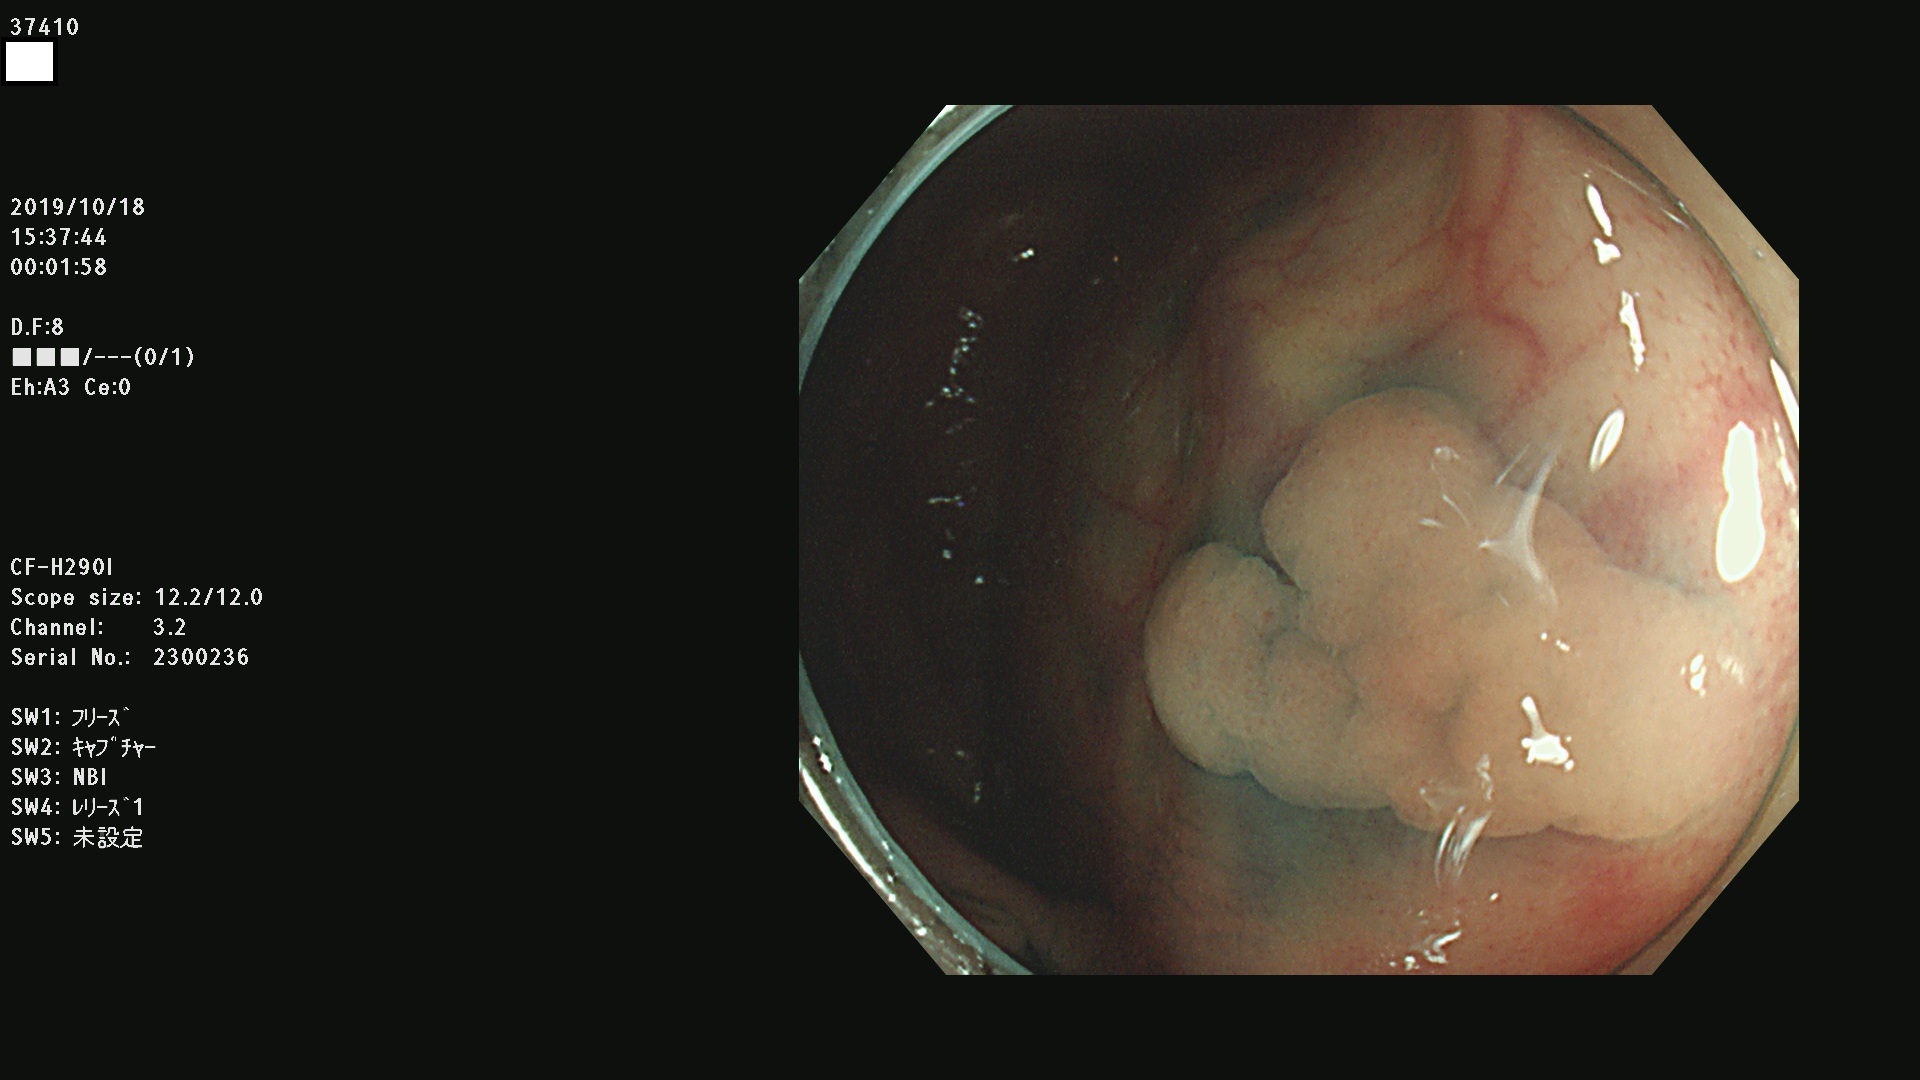

37400(SSAPのみ) 37401 37403 37404 37405 37406 37407 37408 37410 37411 37412 37413 37415 37416 37417 37420 37423 37424 37425 37426 37428 37430(SSAPのみ) 37432 37433 37434 37435 37436 37437 37438 37439 37440 37442 37443 37444 37447 37448 37449 37450 37451 37452 37455 37456 37457 37458 37459 37460 37461 37462 37464 37467 37468 37469 37470(SSAPのみ) 37471 37472 37474 37476(SSAPのみ) 37477 37478 37480 37481 37482 37483 37485 37486 37487 37488 37489 37490 37491 37492 37493 37494 37497 37499

発見困難で危険性の高い平坦型病変(上記100名より抽出)